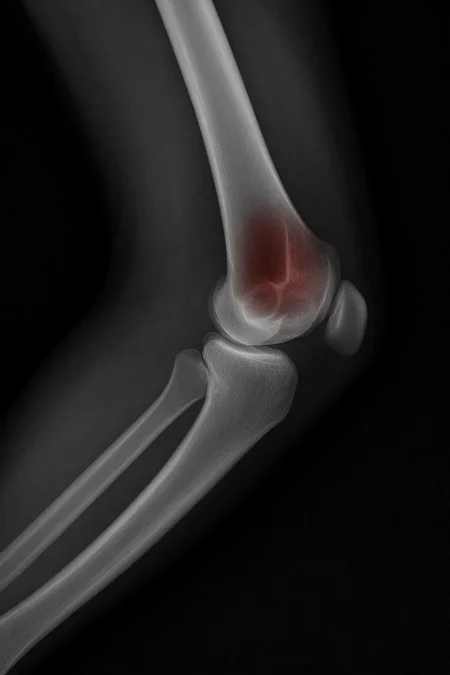

Can a model like Flux Kontext, designed for editing art and photography, be used to work with medical images, for example, with something 'as simple' as red-marking fractures?

The quick answer: it does do something interesting, but it over-scores and is far from reliable as a medical tool. It's a prototype to play with the idea, nothing more.

2. Ask: “Make marks where there is a fracture”.

With a synthetic mini-dataset for Civitai of images made with 100% AI (10 healthy X-rays and 10 fractured):

False positives: 100% in healthy bones.

Fracture detection: ≈ 45%